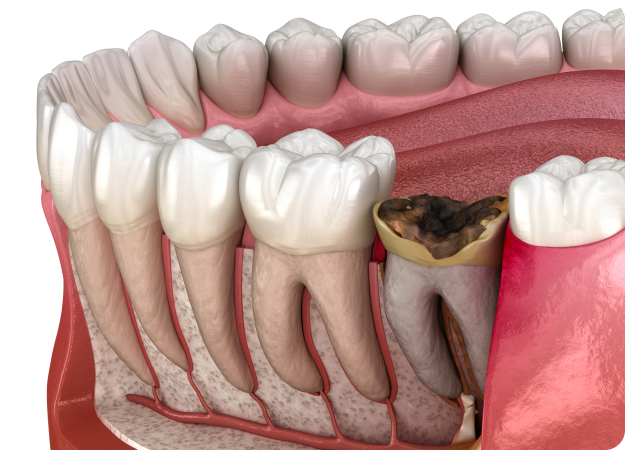

충치&신경 재치료.

충치 재치료

처음 충치 치료를 할 때 대부분 보철물을 씌우는 충전치료를 하는데요, 치아와의 틈이나 경계 없이 치료가 이루어집니다. 보철물의 수명은 관리에 따라 다르지만 보통 5~8년 정도로 시간이 지나면 재료도 오래되고, 치아의 틈 사이로 음식물이 낄 수 있습니다. 제대로 제거가 되지 않으면 2차 충치가 생기기도 합니다. 또한 입안에는 항상 세균이 상주하고 있어 관리가 소홀해지면 충치가 발생하기 쉽습니다.

신경 재치료

신경치료 근관의 개수, 길이, 굵기 등을 측정한 후 치수를 제거하고 근관을 세척해 미세한 근관까지 소독한 후 근관 충전을 하는 방식으로 치료합니다. 그러나 치료 후에도 지속해서 통증이 남아있다면 신경재치료가 필요합니다.

증상이 나타났을 때는 이미 치아 손상이 심하게 된 경우입니다.

충치는 자각 증상이 없어 발견하기 어려우므로

정기 점검을 받아야 합니다.